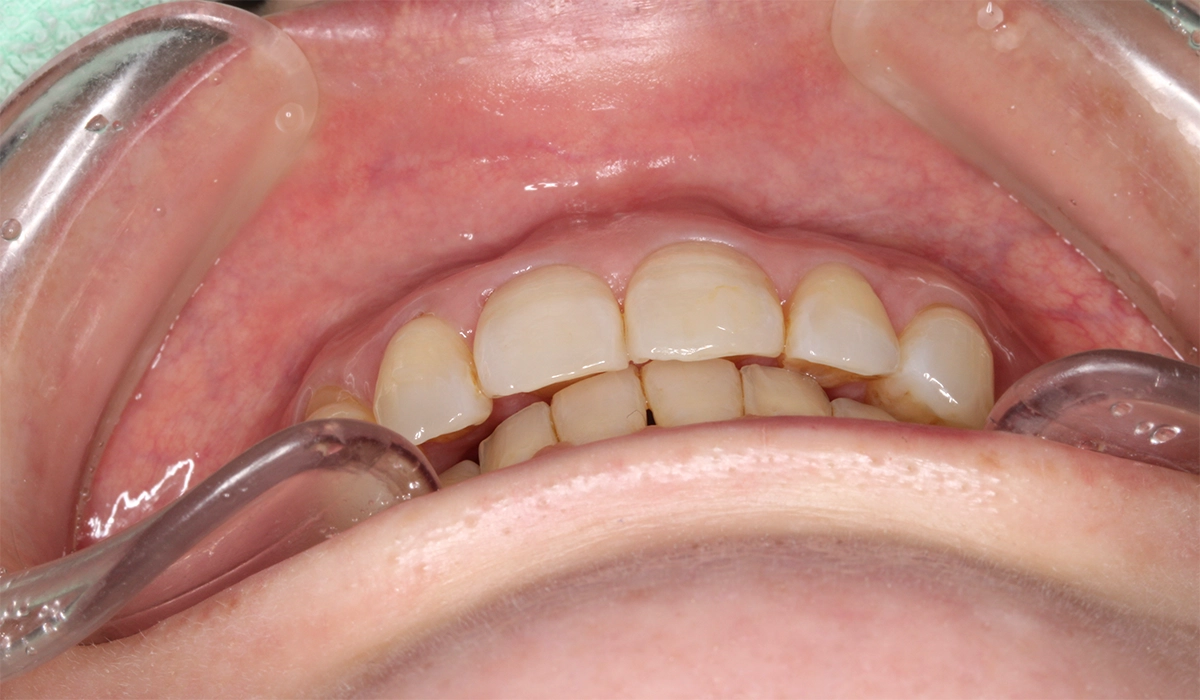

術前:正面